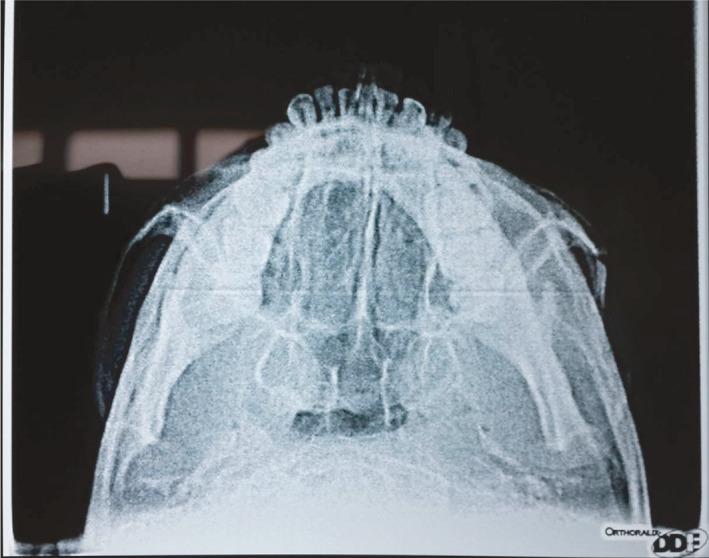

Zygomatic arch fractures are the most common facial fractures or second in frequency after the nasal fractures. The high incidence of zygomatic fractures probably relates to its prominent position in the facial skeleton; hence, it is frequently exposed to fractures. This case report presents an left-sided isolated zygomatic arch fracture after subjected to routine investigations and radiographs like submentovertex and CT scans. The patient was operated under general anesthesia for the reduction of zygomatic arch by Gille's temporal approach with the use of Ultrasound intra-operatively. Recommendation for the use of ultrasonography in the identification of zygomatic arch fractures intra-operatively operatively.

https://cdn.ncbi.nlm.nih.gov/pmc/blobs/0c51/8582023/38efa8ed31e6/CCR3-9-e05067-g008.jpg